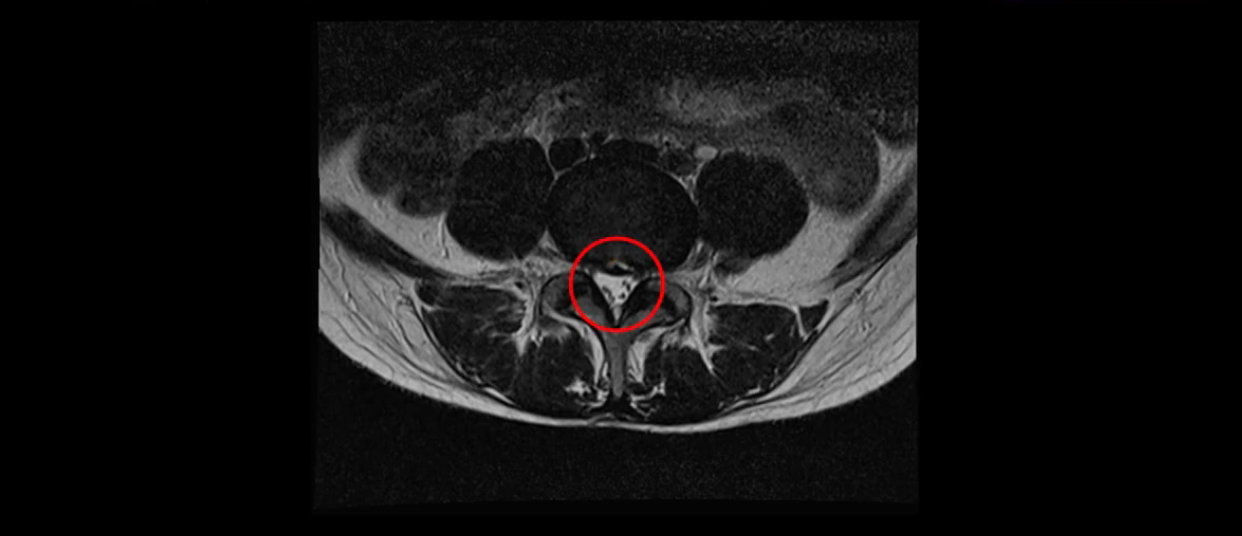

이분 MRI를 보시면 두 마디의 퇴행성디스크가 있습니다. 그리고 디스크가 조금씩 밀려 나와 있고요. 그런데 디스크 탈출 정도는 두 마디 다 심하지 않습니다. 4번 5번에는 디스크 탈출이 약간 있고,

중요한 것은 이 정도 경미한 탈출과 협착으로는 양쪽 다리가 저리고 아플 수가 없습니다.

이분 MRI를 보시면 퇴행성디스크가 있고 약간의 협착이 있지만 이 정도의 퇴행성디스크와 협착으로는 신경이 눌려서 양쪽 다리가 저리고 아픈 증상이 나올 수가 없습니다. 그래서 MRI와 이 환자분의 다리 증상이 매치가 안 된다고 하는 의사들이 많은 겁니다.